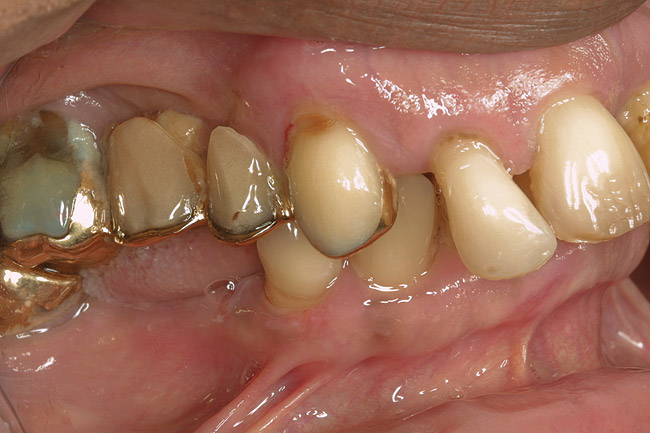

Stage 2 Demineralization (D2)

D2 root-surface lesions (Figure 3) are characterized by the dull surface demonstrated with D1 root-surface lesions. In addition, the surface feels sticky and somewhat soft when palpating with the side of the explorer. The examiner may notice that the root surface slightly resists gentle exploration over the root surface with the side of the explorer. Color changes in D2 root-surface lesions may range from dark yellow to orange/light brown. No cavitation of the root surface exists. The recommended treatment for D2 root-surface lesions includes remineralization with products (pastes and varnishes) containing fluoride, calcium, and phosphate. If the area is in the esthetic zone, the patient may request restoration, despite intact root structure.

It is common for practitioners to press the tip of the explorer into these root surfaces and decide to restore these “carious” areas. When pressing an explorer into a D2 root surface, a clinician may feel a definite softened surface or a “stick.” It is vital to either use the side of the explorer or visual inspection when determining these lesions. Aggressive exploration with the tip of the explorer may cavitate these root surfaces, which can lead to mechanical damage of the root surface and a decrease of the likelihood of successfully remineralizing the surface.

Figure 2  The root surface cervical to the crown margin appears darker than healthy cementum. In addition, the surface appears dull. When palpated with the side of an explorer, the clinician can expect to feel a root surface that resists the explorer over its surface.

Figure 2